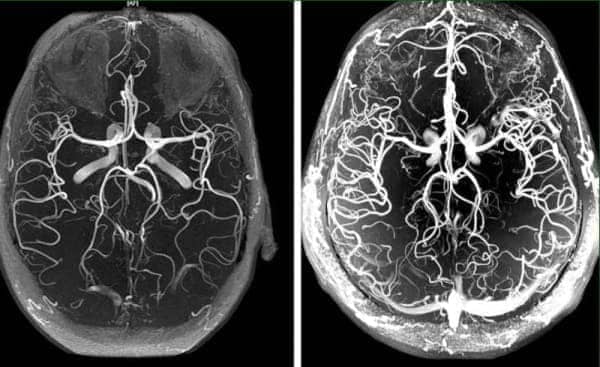

kép

Az eltömődött erek a szervezet összes létfontosságú rendszerének hibás működéséhez vezetnek.

A vérkeringés szisztémásan helyreáll - minden érben, artériában és hajszálérben.